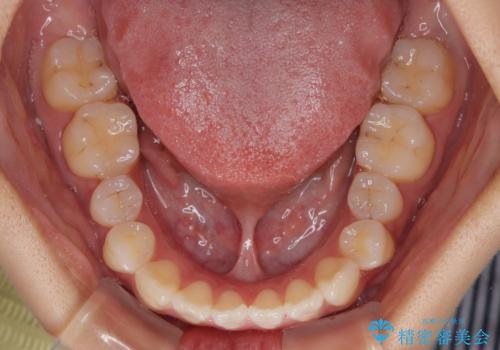

- 前歯の開咬を気にして来院された患者様です。

開咬の治療は、前歯を閉じるように動かすとともに、上下臼歯を圧下(骨内にめり込ませる)させることで進めて行きます。

インビザラインは臼歯の圧下を効果的に行えるため、インビザラインを用いて矯正治療を行うこととしました。